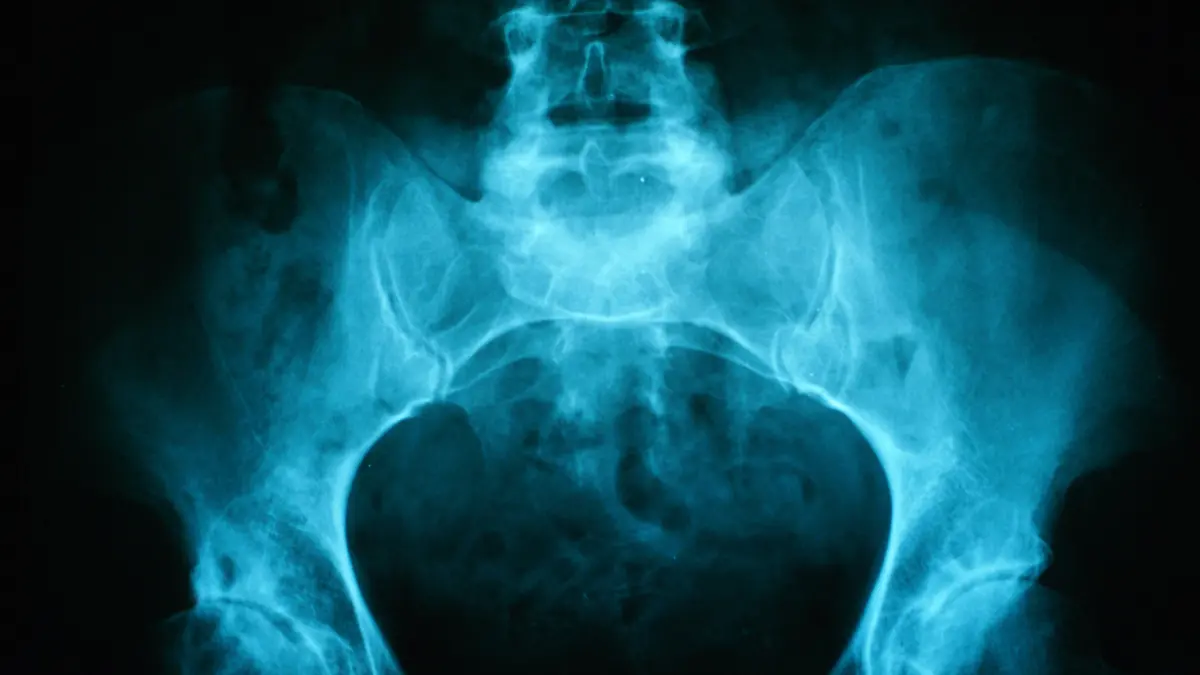

Die unterschiedlichen organischen Stoffe im menschlichen Körper reagieren verschieden auf Bestrahlung. Dadurch, dass beispielsweise Knochen weniger strahlungsdurchlässig sind als Weichteile, und luftgefülltes Gewebe durchlässiger ist als anderes Gewebe, ergeben sich Bilder des inneren Organismus, die der Radiologe auf Auffälligkeiten untersuchen kann. Das früheste radiologische Verfahren ist die Anwendung von Röntgenstrahlen. Inzwischen sind Computertomografie (CT), Magnetresonanztherapie (MRT) und Ultraschalluntersuchungen (auch Sonografie) hinzugekommen. Sie alle bieten dem Arzt einen Einblick in das Innere des Körpers, ohne diesen chirurgisch öffnen zu müssen. Minimalinvasive Eingriffe, zum Beispiel in Form einer Herzkatheteruntersuchung, sind in der Radiologie jedoch zuweilen auch vonnöten. Durch den diagnostischen Einblick, den radiologische Untersuchungen in den Organismus ermöglichen, soll der Arzt zu einer sicheren Diagnose kommen. Die Radiologie kann jedoch auch Behandlungsmöglichkeiten stellen, beispielsweise in der Strahlentherapie. Die bekannteste Verwendung dürfte die Bestrahlung von Tumoren sein, was häufig mit einer Chemotherapie kombiniert wird.